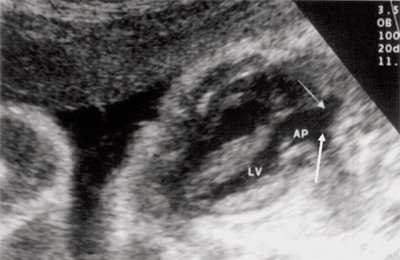

При эхокардиографии изучались четырехкамерный срез сердца плода (рис. 1) и срез через три сосуда (рис. 2). УЗИ проводилось трансабдоминальным датчиком, лишь при необходимости (затрудненная визуализация) использовался внутриполостной датчик. Четырехкамерный срез сердца плода при ультразвуковом сканировании трансабдоминальным датчиком визуализировался в 85% случаев, срез через сосуды - в 73%, при использовании трансвагинального датчика эти цифры существенно возрастали до 100 и 91% соответственно. Оптимизация пренатальной диагностики ВПС может быть достигнута путем строгого соблюдения основных методических правил. При оценке четырехкамерного среза плода необходимо оценить нормальное расположение сердца плода, исключив его эктопию (рис. 3), положение оси сердца плода, что не представляет никаких трудностей, нормальные пропорции и размеры камер сердца, движение створок атриовентрикулярных клапанов должно быть свободным, септальная створка трикуспидального клапана должна располагаться ближе к верхушке сердца (рис. 4). При оценке среза через три сосуда необходимо оценить взаиморасположение сосудов и их диаметр.

Рис. 1. Беременность 12 недель. Четырехкамерный срез сердца плода. Отчетливо видны камеры сердца.